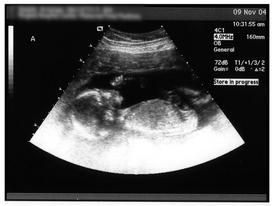

posted 11.09.2004 by Kristen Had another ultrasound today at 19 weeks, 5 days. This was the official Level II ultrasound, where they crefully check all the structures and organs for any sign of abnormalities. Luckily we passed with flyng colors! The babies are growing right on target. Baby A is estimated at 11 oz., and Baby B is estimated at 12 oz., so they've both doubled in weight since last month's ultrasound. It's really incredible how quickly they grow. And of course the most exciting news! We have GIRLS! Let the shopping begin! Oh, and how cute -- Baby A was sucking her thumb! Baby B was sort of turned toward my back, so you can't see much detail on her today.